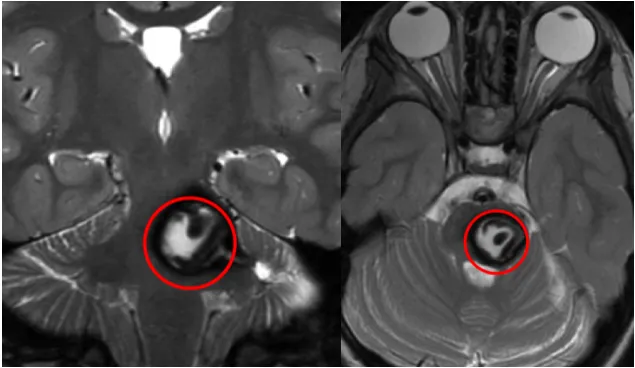

一個月前,還和其他孩子一樣奔跑嬉戲的阿莉莎毫無征兆地出現(xiàn)劇烈頭痛、嘔吐,病情迅速發(fā)展到右側身體逐漸失靈,面部歪斜。 輾轉就醫(yī)后,MRI結果顯示:腦橋巨大海綿狀血管瘤出血,伴多...